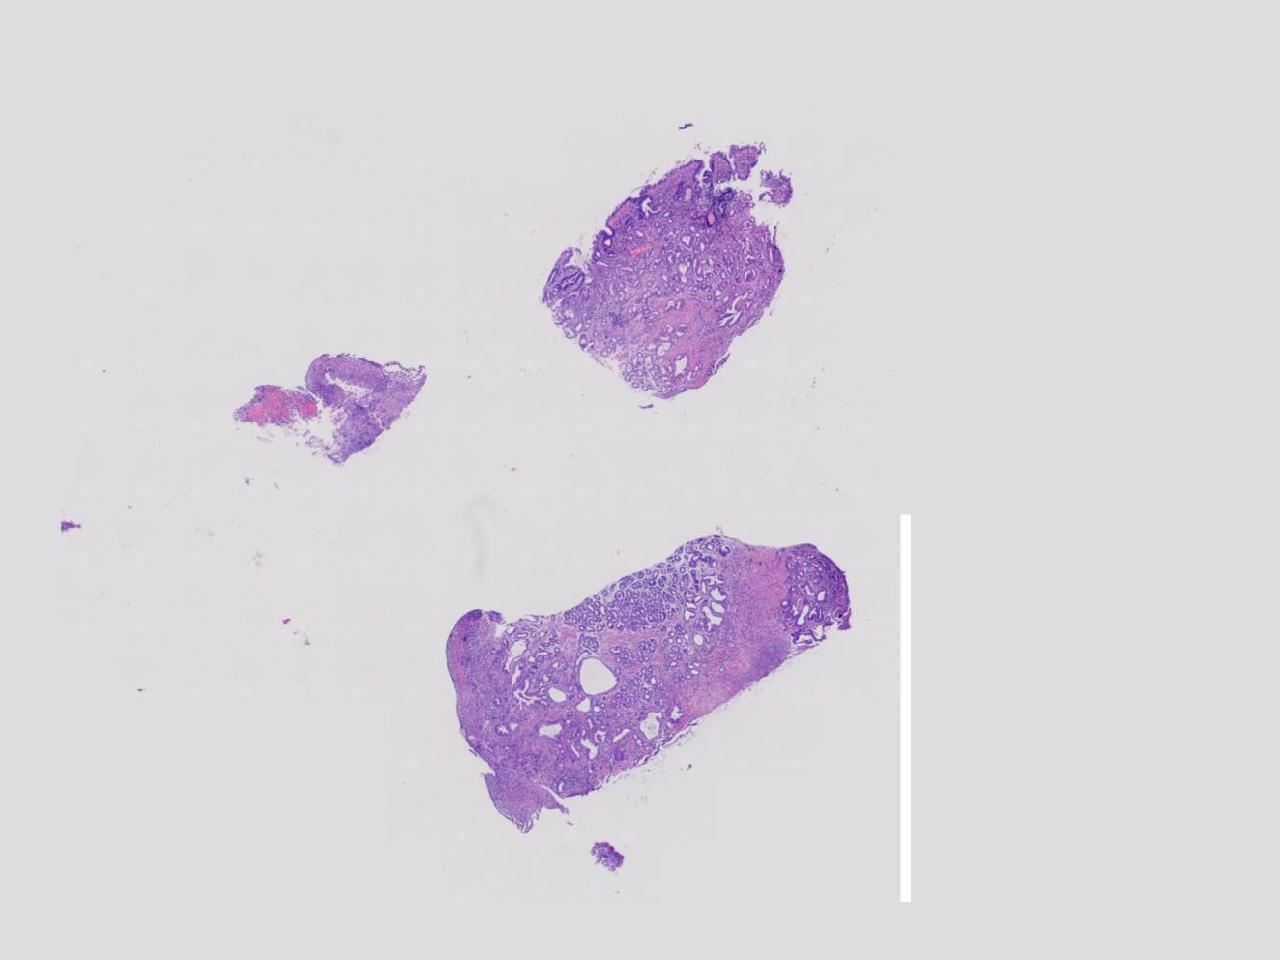

胃体上部见一大小约2厘米的溃疡灶,表覆白苔,周边充血,水肿明显,活检3块。

胃体活检

灰白色不整形软组织3块,直径均0.2厘米。

深在性囊性胃炎,少量溃疡组织

深在性囊性胃炎伴溃疡